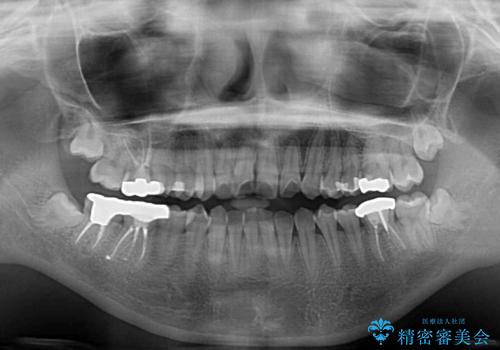

- 上下歯列全体のデコボコを気にして来院された患者様です。

主に下顎歯列全体の後方移動とIPR(歯と歯の間を削る)によってデコボコが解消するように設計し、インビザラインにより治療を行うこととしました。

1年半程度で終了するのではないかと予想しましたが、途中1年以上の来院がなく、トータルで3年の時間がかかってしまいました。

前歯のデコボコはより改善することが望ましい状態でしたが、患者様の希望により終了することとなりました。